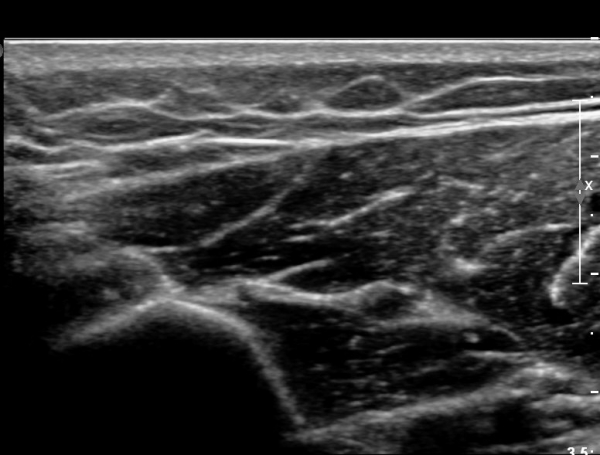

ŽÃËÀÚ¸¦ Á¶±Ý ¸»´ÜÀ¸·Î À̵¿ÇÏ´Ï ¿ä°ñ½Å°æ Àú¿¡ÄÚ ºÎÁ¾ÀÌ ´õ¿í ¶Ñ·ÈÇѵ¥(»çÁø 2),

ŽÃÊÀÚ¸¦ Á¶±Ý ´õ ¸»´ÜÀ¸·Î À̵¿ÇÏ´Ï ¿ä°ñ½Å°æÀÌ °üÂûµÇÁö ¾Ê°í(»çÁø3),

Á¶±Ý ´õ ¸»´ÜÀ¸·Î À̵¿ÇÏ´Ï ´Ù½Ã Àú¿¡ÄÚ ºÎÁ¾ »óÅ·Π°üÂûµÈ´Ù(»çÁø 4).

ÀÌ·± ÀÏ·ÃÀÇ °úÁ¤Àº ÷ºÎ µ¿¿µ»ó¿¡¼ ¶Ñ·ÈÈ÷ °üÂûµÈ´Ù.